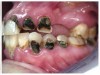

Often, the most visually striking manifestation of long-term meth use—known as “meth mouth”—is caused by the lack of saliva combined with an increase in soda drinking and extremely poor oral hygiene. This typically leads to meth abusers experiencing a large amount of caries. Decay begins with occlusal and facial caries and progresses rapidly, decaying to the bone level and often leaving only roots (Figure 1 through Figure 3).16

Fig 1. Radiographs showing an example of “meth mouth.”

Figure 1

Fig 2. Gross oral destruction was the result of more than 20 years of meth use in this 41-year-old woman.

Figure 2

Fig 3. After 5 years of meth use in a 22-year-old male patient, cervical decay and coronal fractures were evident.

Figure 3